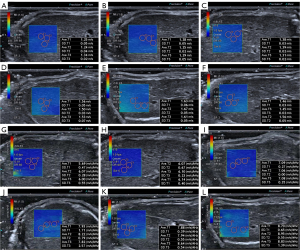

The US values of each group are shown in Figure 5 and Table 1. The SW speed and SWD slope values rose over time compared to the control group, as shown in Figure 6. The 1 w group did not significantly differ in SW speed or SWD slope (P>0.05). There was no significant increase in SW speed in the 2 w group (median: 1.38, IQR: 1.29 to 1.39) (P>0.05), but SWD slope values were significantly higher (median: 7.26, IQR: 7.04 to 7.31) (P<0.05). The SW speed and SWD slope values of the 3–5 w groups increased continuously (P<0.05), but there was no significant difference among the 3 groups (P>0.05). The SWD measurements provided excellent interobserver and intraobserver consistency. For interobserver variability in SW speed and SWD slope values, the ICC was 0.816 (95% CI: 0.64 to 0.91) and 0.838 (95% CI: 0.68–0.92), respectively. For intraobserver variability in SW speed and SWD slope values, the ICC was 0.801 (95% CI: 0.61 to 0.90) and 0.823 (95% CI: 0.65 to 0.91), respectively.

There were significant differences in SW speed and SWD slope among the control group, nGVHD group, and aGVHD group (P<0.001). In the pairwise comparison, SW speed in nGVHD group (mean ± SD: 1.38±0.15, 95% CI: 1.29 to 1.46) was not significantly different from that in the control group (mean ± SD: 1.27±0.08, 95% CI: 1.19 to 1.36), but SWD slope (mean ± SD: 7.00±1.11, 95% CI: 6.36 to 7.64) was significantly higher than that in the control group (mean ± SD: 5.92±0.42, 95% CI: 5.48 to 6.35). The aGVHD group’s SW speed (mean ± SD: 1.54±0.11, 95% CI: 1.48 to 1.59) and SWD slope (mean ± SD: 8.29±0.56, 95% CI: 7.99 to 8.59) were significantly higher than those of the nGVHD and control groups.